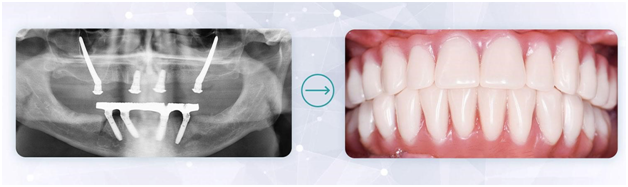

В норме живые здоровые зубы присутствуют у человека до 7-х или 8-х позиций на каждой челюсти. Рассказываем, сколько коронок выдержат 4 импланта. Фото: Smile-at-Once.ru.

Посмотрите на фото – это как раз адаптационный протез, установленный на 3-4 день после имплантации all-on-4. В данном примере – с добавлением скуловых моделей NobelZygoma для реабилитации верхней челюсти.

Смотрите, как гармонично выглядит улыбка нашей пациентки на всех этапах протезирования после All-on-4.